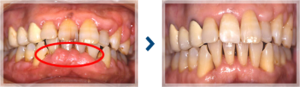

軽度歯周病の治療例

歯周病により歯肉が増殖している状態を治療により改善